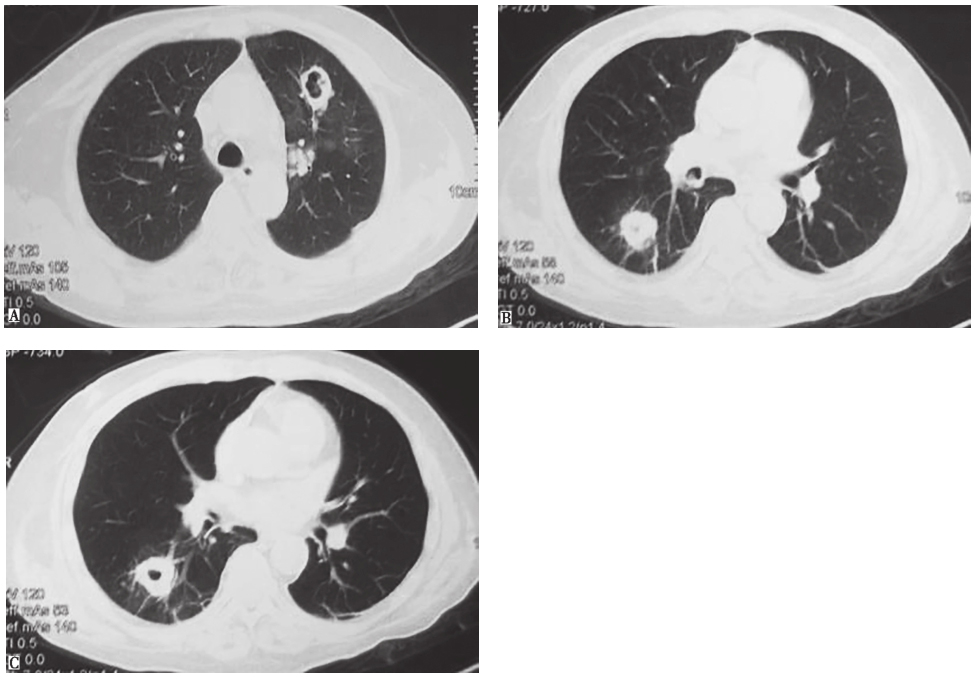

图5|胸部CT表现(2009-11-19)

胸部CT示双肺多发结节、空洞影

在内分泌科,针对库欣综合征进行了全面检查。腹部增强CT示双侧肾上腺增生,垂体磁共振成像(magnetic resonance imaging,MRI)未见异常,结合大/小剂量地塞米松抑制试验、血浆促肾上腺皮质激素(adrenocorticotropic hormone,ACTH)浓度、24小时尿游离皮质醇、促肾上腺皮质激素释放激素(corticotropin releasing hormone,CRH)兴奋试验等检查结果,考虑异位ACTH综合征可能性大。11月9日查胸部CT,见双肺散在小结节、斑片影,双侧少量胸腔积液。11月17日,患者再次出现咳嗽、痰中带血丝,伴低热(最高体温37.9℃),复查X线胸片见双肺多发结节影,加用莫西沙星后病情缓解不明显。11月19日复查胸部CT,显示双肺多发结节、空洞影(图5)。为进一步诊疗,患者转入我院呼吸内科(患者自11月4日来我院急诊至转呼吸科之前,一共用莫西沙星9天)。